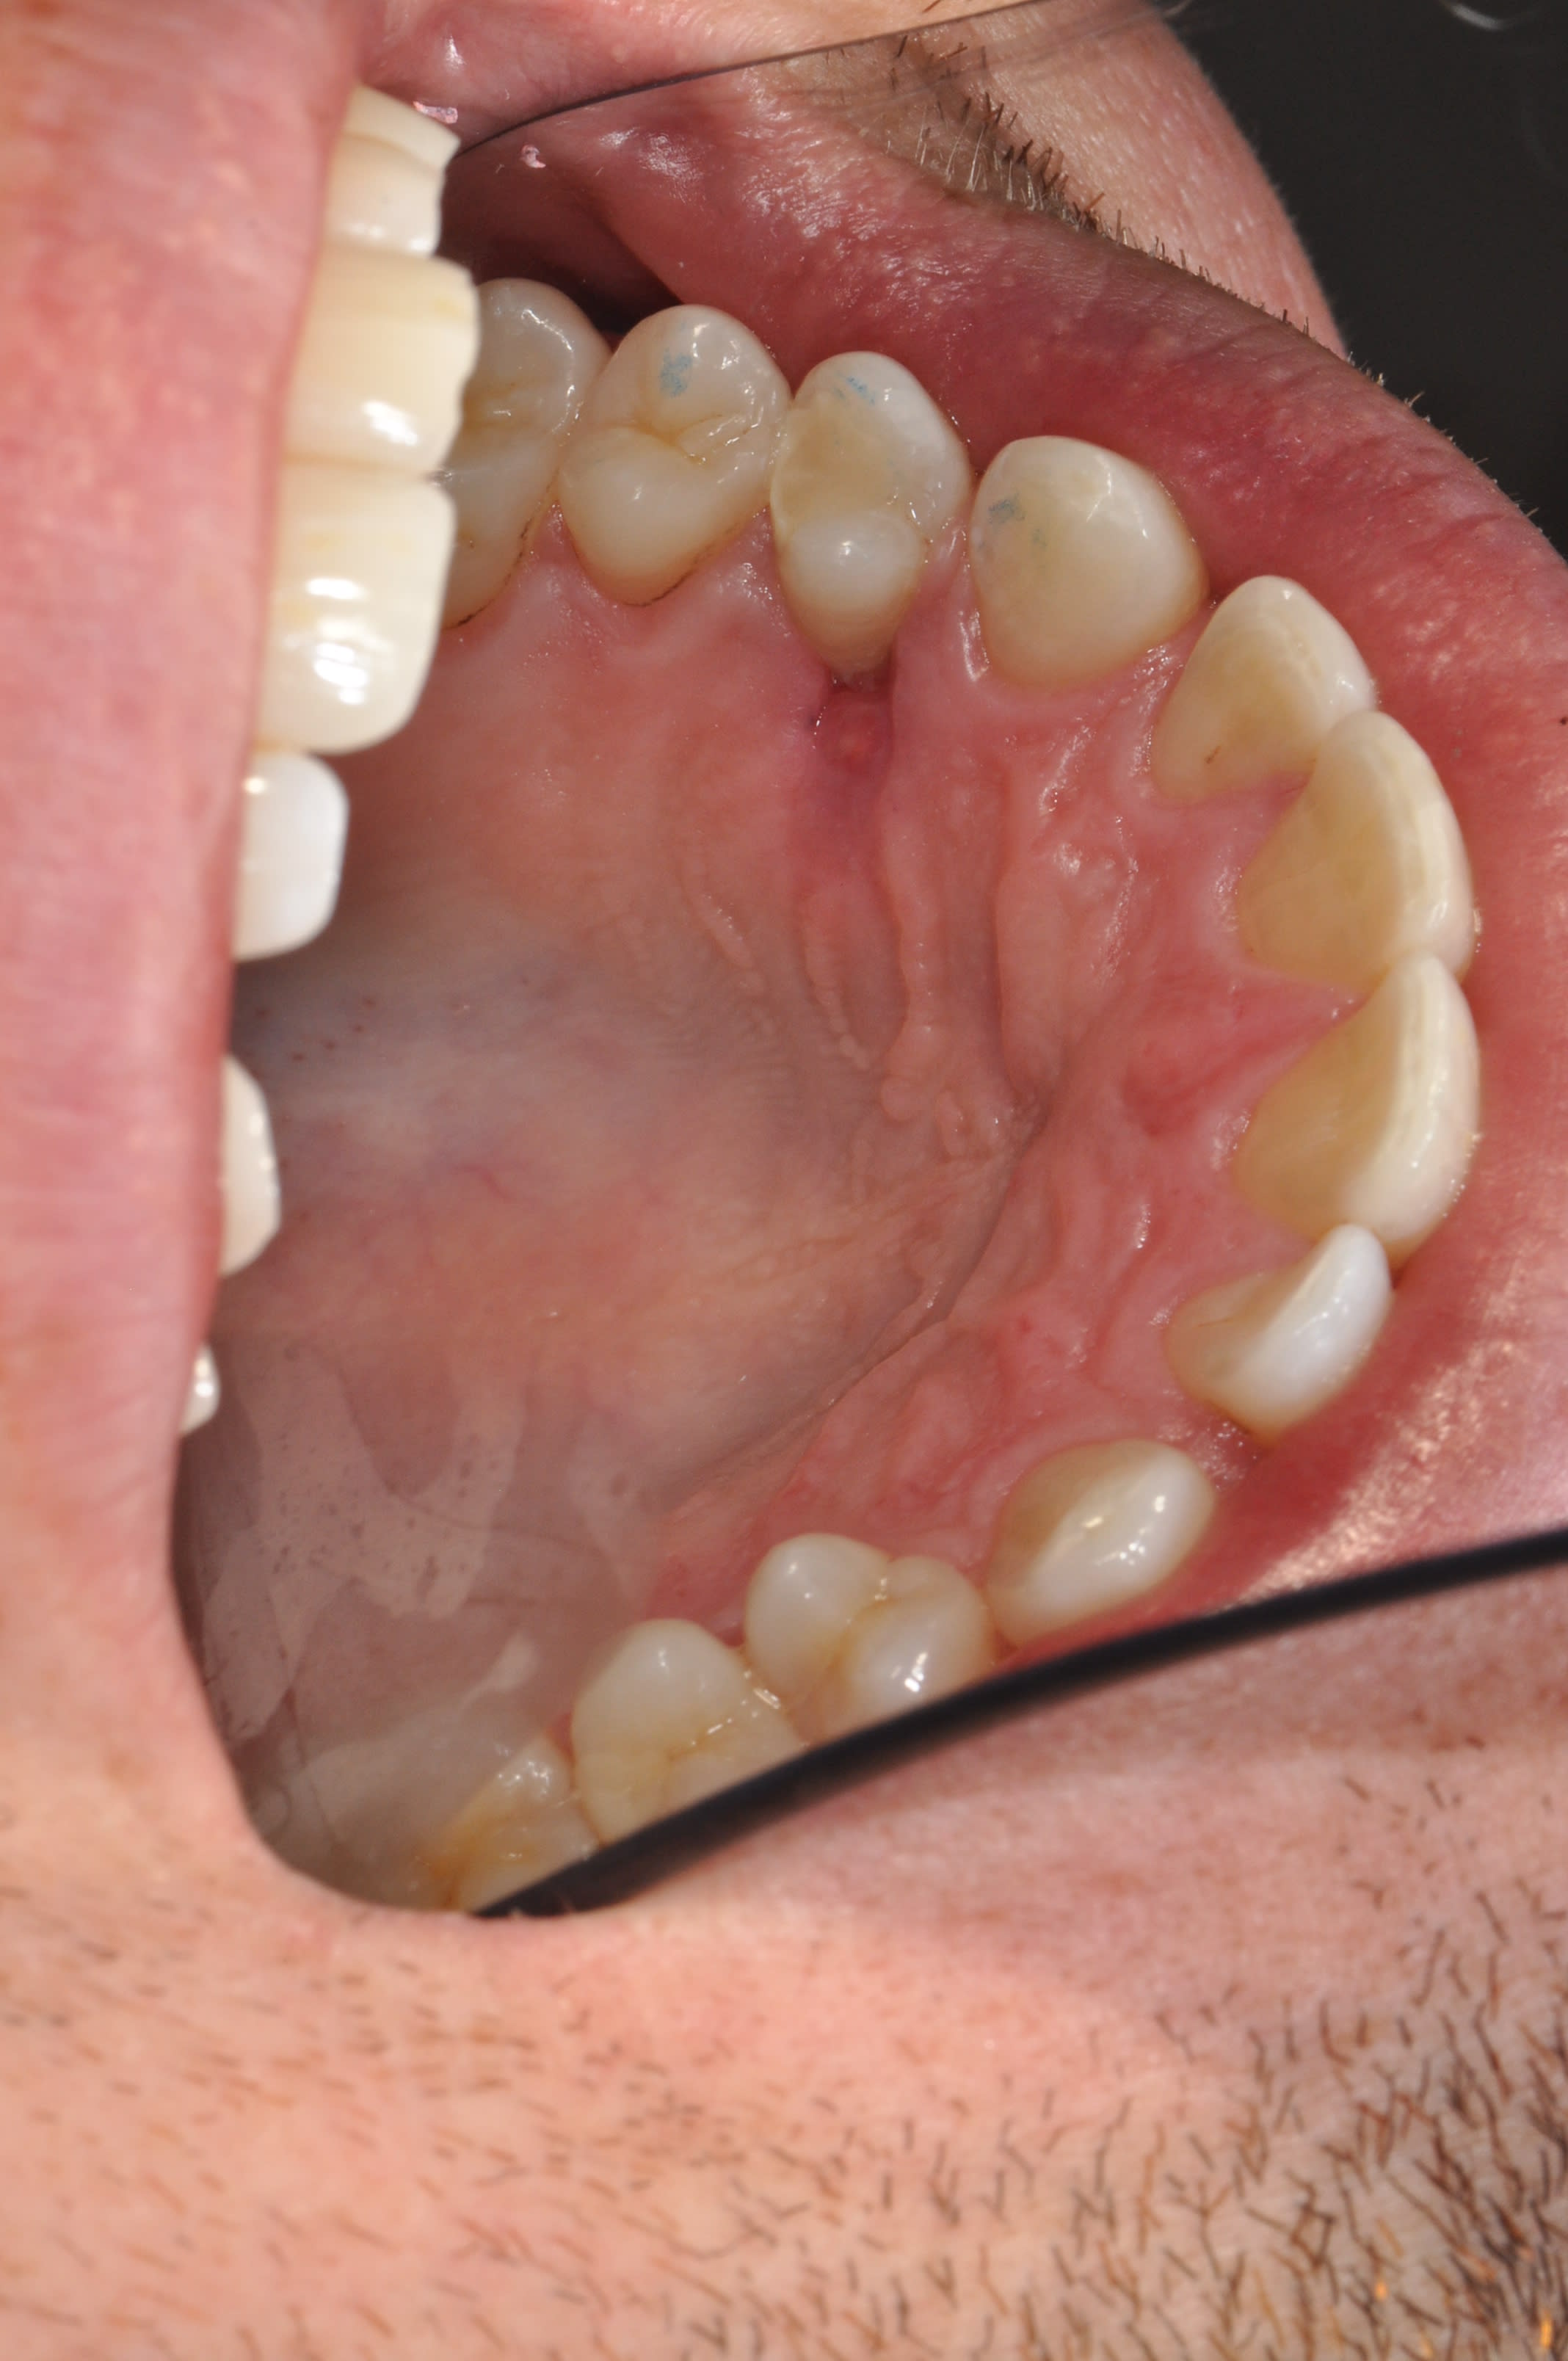

Tiens, une belle nécrose palatine suite à l'endo de cette 24 il y a 15 jours.

- effectivement je ne vérifie jamais la couleur de la muqueuse palatine, c'est un tort (surtout avec du 1/100000),